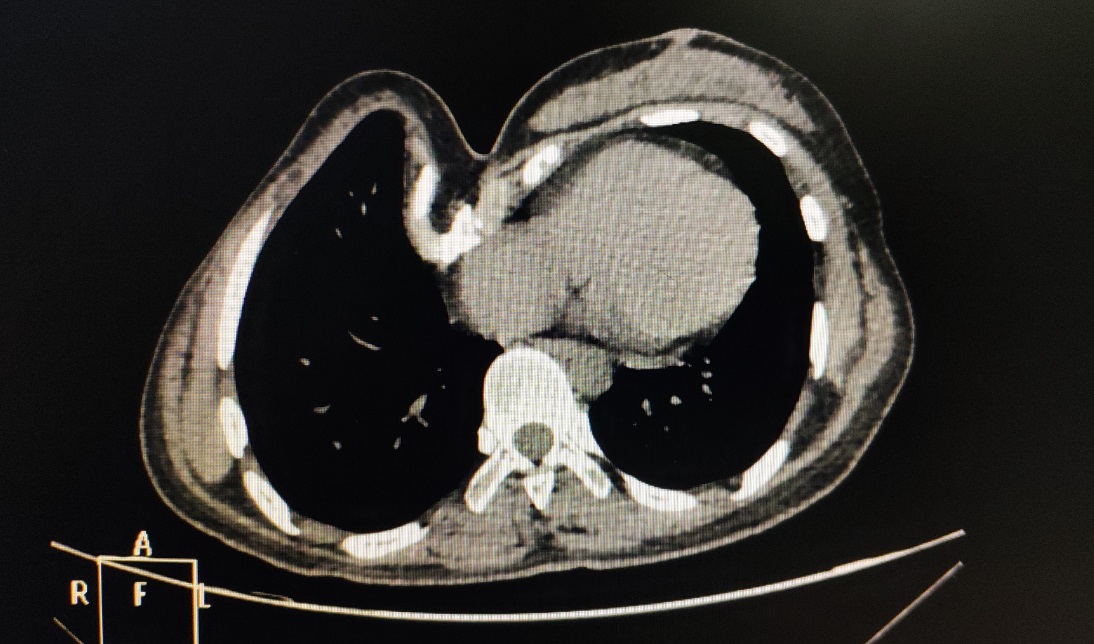

X线检查:正位片见心脏左偏,位于左侧胸腔,左侧肋骨走向异常;侧位片见前胸壁明显畸形。CT检查:前胸壁不对称、不规则型凹陷,凹陷最低处低于脊柱前沿。心脏受压,右侧胸廓严重变形(图1-2)。三维重建:前胸壁极度变形,呈不规则、不对称型凹陷。胸骨体受累,右侧胸壁结构变形严重(图4-6)。

图1,CT提示重度畸形。

图2,CT提示重度畸形。